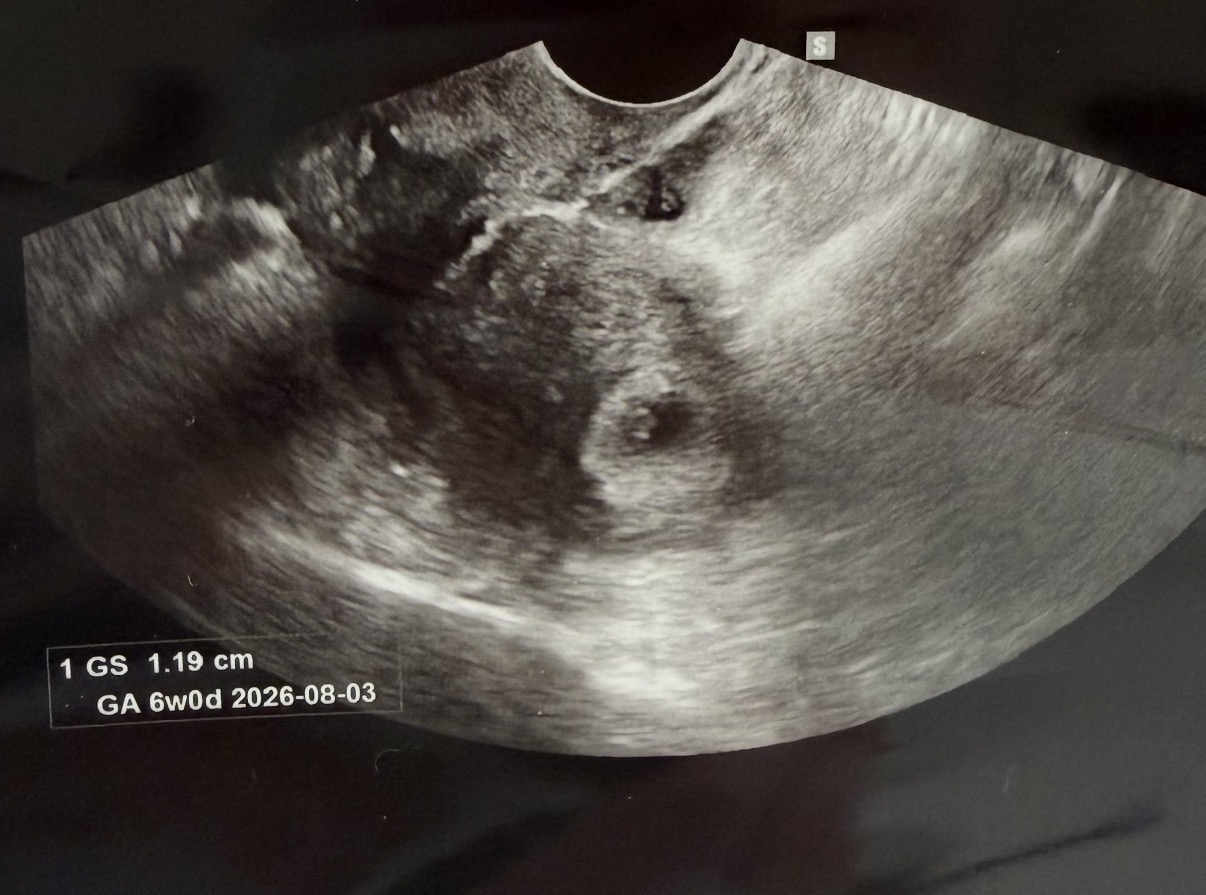

오늘 딱 6주 0일인데 아기집이랑 난황 주수에 맞게 잘 크고 있는거 확인하고 왔네요! 쓰리라임 1번이 확실히 더 진해서 심장소리까지 기대했었는데ㅠ 심소는 못들었어요ㅠㅠ 사정상 7주에 못가고 6주 5일차에 가야하는데 심장소리 잘 들리겠죠~? 걱정인형이라 다녀올때마다 걱정이 +1 되네요ㅋㅋ